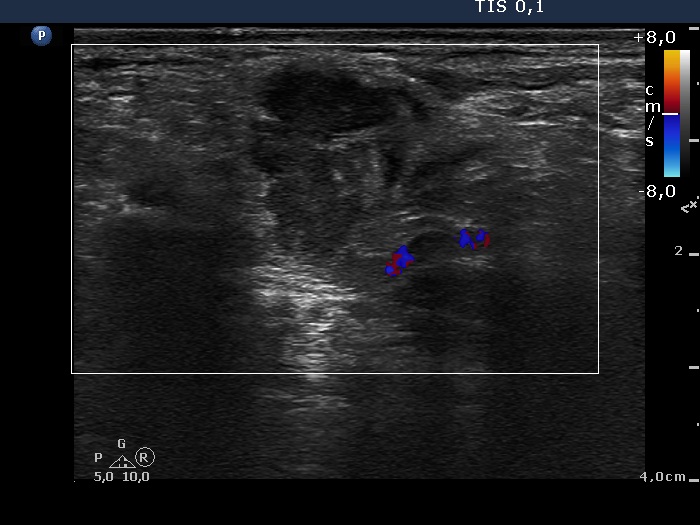

Ultrasonography: The thyroid was intact. There were multiple nodes in both supraclavicular regions. The nodes presented an absolutely irregular shape and border. They contained numerous hyperechogenic circumscribed areas.